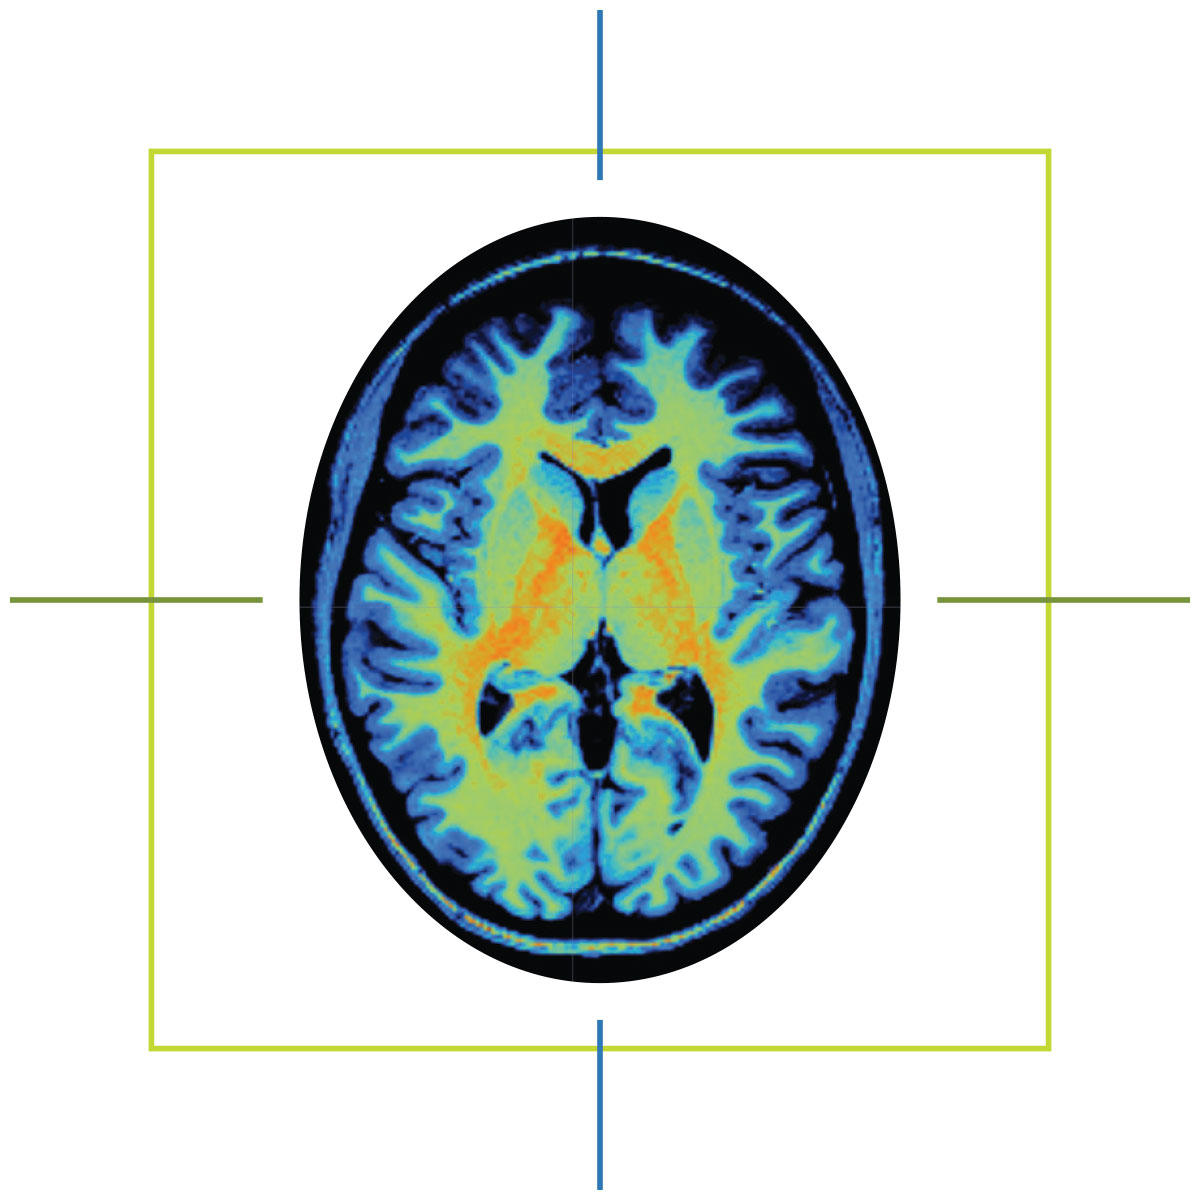

When Marcus Ryninger tells people how his life changed on May 1, 2015, he shows them an MRI scan saved to his phone.

He also knew his speech would never return to how it was before the stroke. But after seeing the scan of his brain — the dark hole of necrotic tissue on one side, the vibrant patchwork of healthy tissue on the other — the man who spent 30 years as a mechanic and quality control supervisor in the Navy understood: The stroke had not taken his determination.

“It helped me see what damage was done,” Marcus says. “I worked on airplanes. You have to find what’s broken and fix it. And the brain, that’s me. I know, ‘Oh, this part is broken. I have to fix this side.’ It made a difference for me.”

Before hospitals began using magnetic resonance imaging machines, or MRIs, for clinical use in the 1980s, physicians had a limited window inside the human body. X-rays could capture images of a patient’s bones. CT scans could even see soft tissues like muscles and organs. But both imaging methods exposed patients to ionizing radiation, and both were poorly suited to distinguish soft tissue variations critical for identifying ligament issues, brain anomalies and some types of tumors.